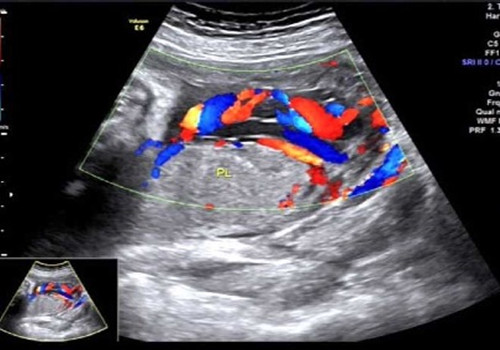

2017年7月10日上午就是在這間小黑屋里,一名34周孕婦正在進(jìn)行產(chǎn)科常規(guī)超聲檢查,當(dāng)探查到胎盤時(shí),朱新娟醫(yī)師一臉凝重,她發(fā)現(xiàn)了異常!經(jīng)科主任吳建軍、副主任醫(yī)師趙瑩會(huì)診,發(fā)現(xiàn)該孕婦腹中胎兒臍帶走形異常、并異常插入胎盤,沿胎膜走行約5.2cm后才進(jìn)入胎盤實(shí)質(zhì),且血管聚集成堆于宮頸內(nèi)口處,考慮臍帶帆狀插入胎盤并血管前置。此現(xiàn)象是非常少見的產(chǎn)科急癥!極易造成血管斷裂!大出血!造成胎兒死亡!而這一切,產(chǎn)婦和家屬卻全然不知。情況緊急,朱新娟立即電話報(bào)告產(chǎn)科危急值!

聲像圖示:臍帶帆狀插入胎盤并血管前置

產(chǎn)科接到危急值報(bào)告后,即刻將該孕婦收治入院,給予密切監(jiān)護(hù)、治療,并于7月20日上午9:40,為該孕婦行剖宮產(chǎn),娩出一名2000g女嬰,母女平安!數(shù)十分鐘后胎盤娩出,確系少見的臍帶帆狀插入胎盤并血管前置!產(chǎn)科馬主任激動(dòng)地拉著吳主任的手說(shuō):“你們超聲醫(yī)生太棒啦!你們就是我們產(chǎn)科醫(yī)生的眼睛!不但救了這對(duì)母女,也‘救’了我們產(chǎn)科醫(yī)生啊!”